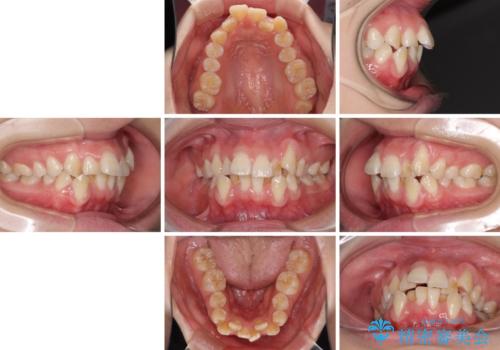

- 上下前歯の叢生と八重歯を気にして来院された患者様です。

前歯部叢生のスペースを獲得するため、上下顎左右小臼歯各1歯を抜歯することとしました。